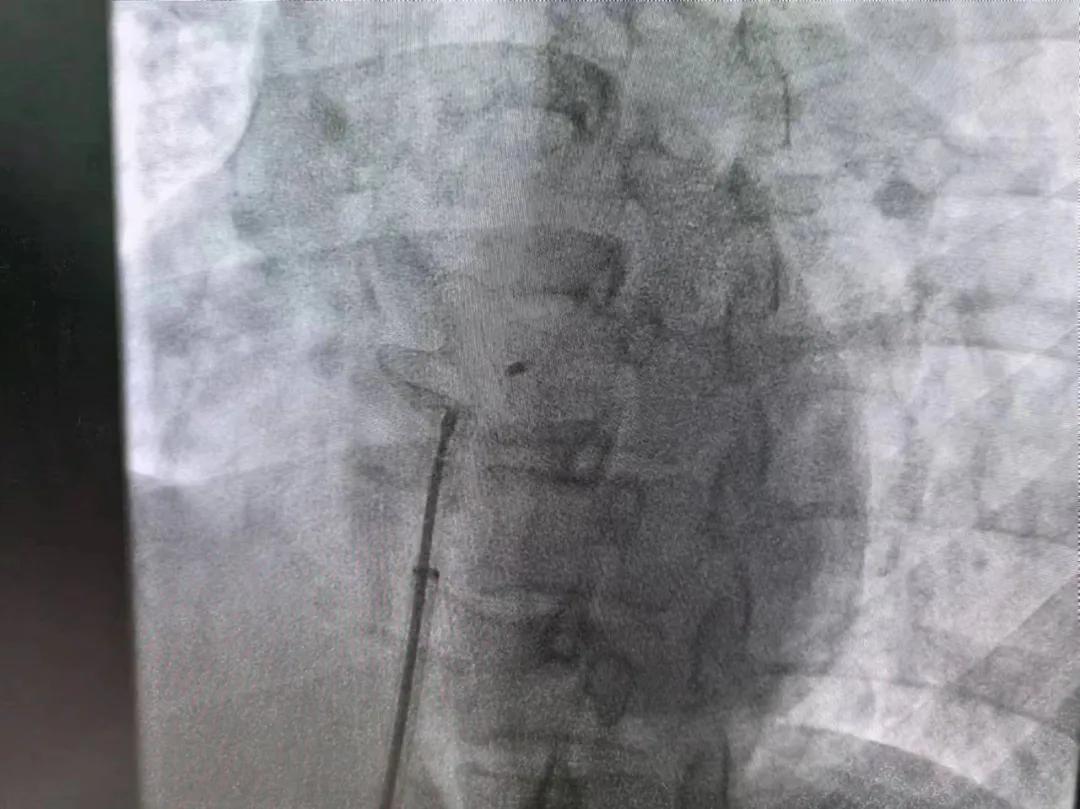

繼3月14日市二院成功開展首例卵圓孔未閉介入封堵術(shù)之后,3月21日上午,市二院院長王瑾及心血管內(nèi)科主任李慧新帶領(lǐng)心血管內(nèi)科介入團(tuán)隊(duì),再次成功為患者實(shí)施“經(jīng)皮房間隔缺損封堵術(shù)”,手術(shù)過程順利。該例病人的成功手術(shù)及康復(fù),標(biāo)志著市二院心血管內(nèi)科在結(jié)構(gòu)性心臟病介入診療中再次達(dá)到了新高度。

患者為中年女性,41歲,近2年一直反復(fù)出現(xiàn)頭暈、頭痛,曾先后在多家醫(yī)院就診。近期患者癥狀加重,出現(xiàn)活動(dòng)后氣喘合并胸悶癥狀,來到心血管內(nèi)科就診。經(jīng)心臟彩超檢查顯示:患者房間隔下段連續(xù)性中斷,缺損直徑達(dá)到了13mm,肺動(dòng)脈壓已經(jīng)輕度增高,確診為房間隔缺損。

于是,院長王瑾會(huì)診后,詳細(xì)詢問患者病史,認(rèn)真分析臨床癥候群并準(zhǔn)確診斷,耐心做好患者及家屬病情告知和充分溝通。經(jīng)過完善的術(shù)前評(píng)估及準(zhǔn)備,心血管內(nèi)科介入團(tuán)隊(duì)成功為患者實(shí)施“經(jīng)皮房間隔缺損封堵術(shù)”,手術(shù)過程順利。近日,患者已順利康復(fù)出院。 (尹紅婭 潘長林)